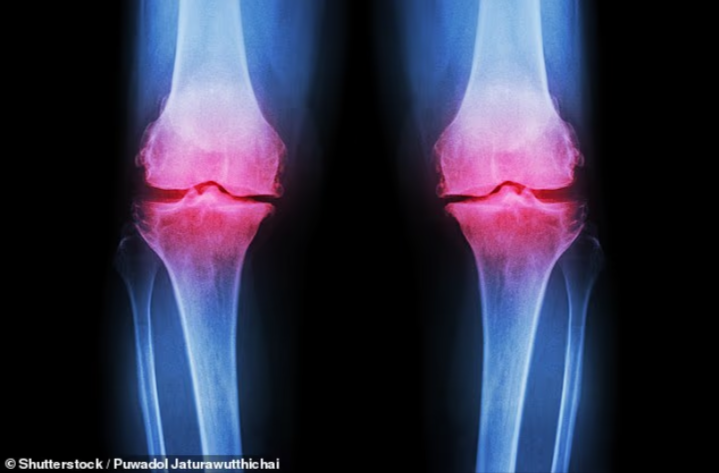

ويأتي ذلك في وقت يعاني فيه أكثر من 3 ملايين شخص في المملكة المتحدة من هشاشة العظام، بينما يُقدَّر أن نحو 40% من الأشخاص فوق سن الخمسين يعانون من “هشاشة العظام المبكرة”، وهي المرحلة الأولى من ترقق العظام.

هشاشة العظام.. خطر صامت

وتتطور هشاشة العظام ببطء على مدار سنوات، وغالبًا لا يتم اكتشافها إلا بعد حدوث كسر نتيجة سقوط بسيط. وتكون النساء أكثر عرضة للإصابة، خاصة بعد انقطاع الطمث بسبب الانخفاض السريع في كثافة العظام.